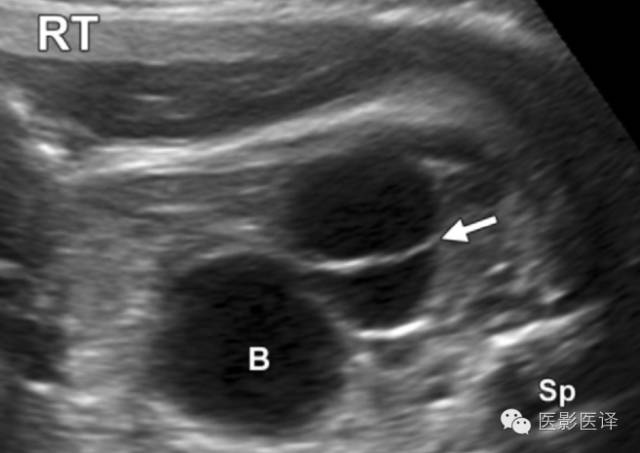

图2:有单分隔的卵巢囊肿:轴位胎儿超声图像显示一个边界清楚有单一薄壁分隔的(箭)腹内囊肿。囊肿位于膀胱外侧,并在其他图像中显示独立于肾脏和胃肠道。超声多普勒图像(未展示)提示囊肿内无血管。RT=右侧,Sp=脊柱。